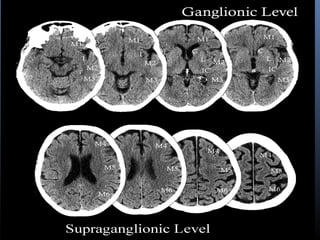

ASPECTS

 The Alberta Stroke Program Early CT Score (ASPECTS) was

proposedin 2001 as a means of quantitatively assessing acute

ischemiaon CT images by using a 10-point topographic scoring

system

 According to this system, the MCA territory is dividedinto 10

regions, each of which accounts for one point in thetotal score

 The normal MCA territory is assigned atotal score of 10. For each

area involved in stroke on the unenhancedCT images, one point is

deducted from that score.

 It was demonstrated thatthe baseline ASPECTS correlated inversely

with the NationalInstitutes of Health Stroke Score (NIHSS), and, as

the ASPECTSdecreases, the probability of dependence, death, and

symptomatichemorrhage increases.